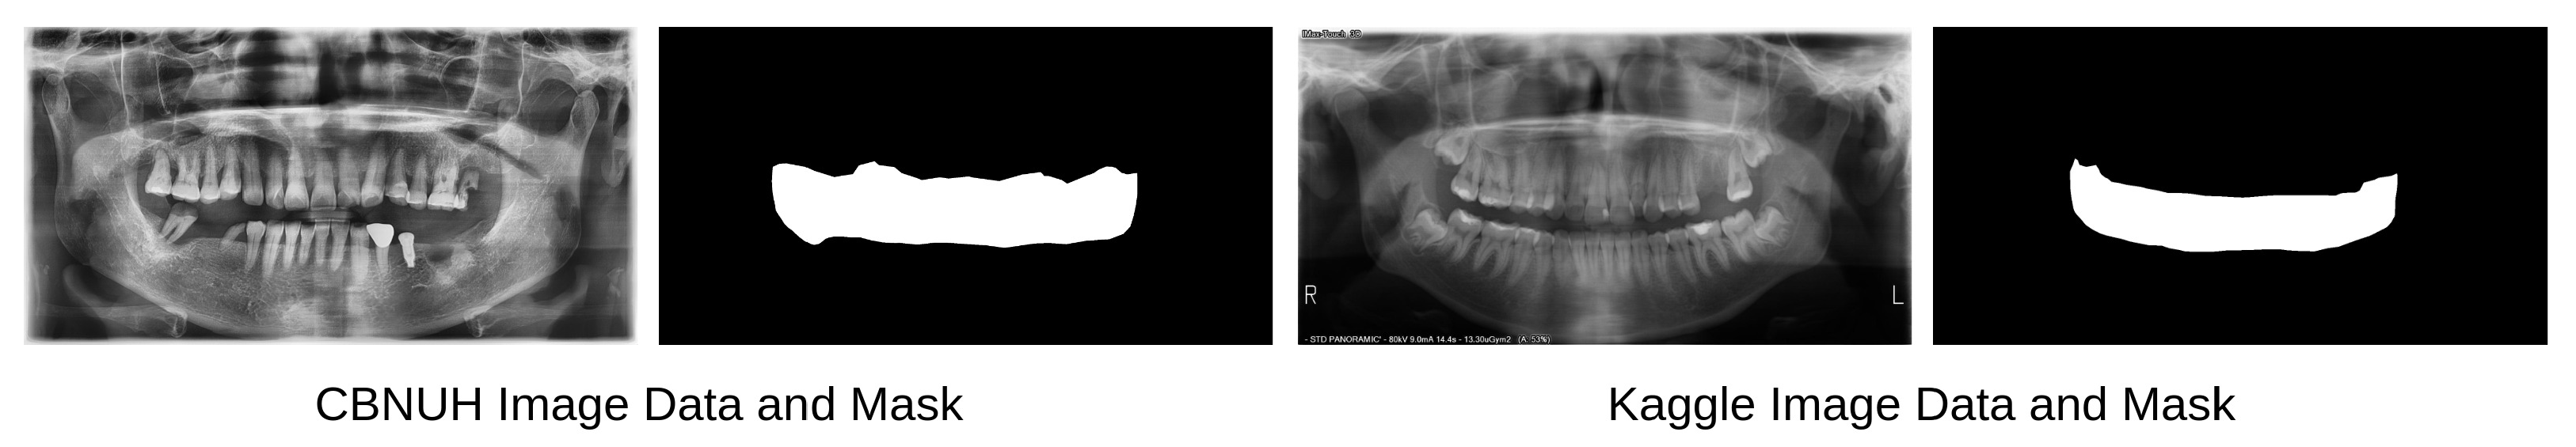

Panoramic radiographs from two different data sources were used in this experiment: the CBNUH dataset and an open-source dataset publicly available in Kaggle [11]. These data were carefully reviewed and manually labeled by professional dentists to ensure that annotated masks were correctly and accurately labeled. The CBNUH dataset was approved by the Institutional Review Board of the CBNUH (CBNUH 2021-11-011) before the experiment began. CBNUH data were collected from 100 patients who underwent upper- and lower-jaw scans during their hospital visits. In the proposed framework, the CBNUH and public datasets were used to train the super-resolution and semantic segmentation models, respectively. Figure 2 shows a random sample image from each data source with its corresponding manually labeled PBL mask.

Figure 2. Samples of panoramic radiographs and PBL masks from each data source.